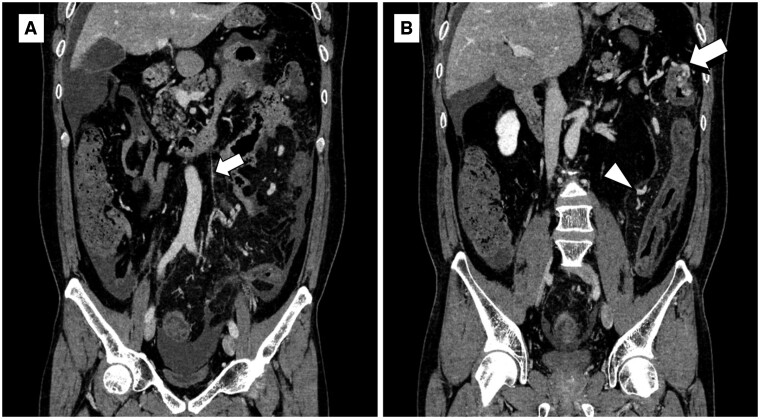

A 44-year-old man presented with a chief complaint of constipation. Initial contrast-enhanced CT showed extensive bowel wall thickening, mainly in the left colon, with a thin cord-like inferior mesenteric vein (IMV), in contrast to ectatic mesenteric venous branches, suggesting bowel ischaemia owing to venous stasis. One month later, at the time of symptom exacerbation, CT angiography showed a cord-like IMV and ectatic mesenteric venous branches with early enhancement, suggesting the presence of an arteriovenous fistula (AVF). Owing to the progression of bowel ischaemia and necrosis with peritonitis, emergency surgery was performed. Surgical specimens showed focal myointimal hyperplasia of the proximal mesenteric veins in both ischaemic and non-ischaemic lesions of the resected colon, thus leading to the diagnosis of idiopathic myointimal hyperplasia of mesenteric veins (IMHMV) when combined with the clinical and imaging findings. IMHMV is a bowel ischaemic disease caused by non-thrombotic venous obstruction that requires bowel resection and has been suggested to be associated with AVF. Cord-like IMV and AVF in the mesentery are important CT findings that characterize IMHMV. CT angiography is useful in diagnosing IMHMV.

一名 44 岁男子以便秘为主诉就诊。最初的造影剂增强 CT 显示肠壁广泛增厚,主要位于左侧结肠,肠系膜下静脉(IMV)呈细绳状,肠系膜静脉分支异位,表明由于静脉瘀血导致肠缺血。一个月后,症状加重时,CT 血管造影显示肠系膜下静脉(IMV)呈条索状,肠系膜静脉分支异位且早期增强,提示存在动静脉瘘(AVF)。由于肠道缺血坏死并伴有腹膜炎,医生对患者进行了紧急手术。手术标本显示,在切除的结肠缺血和非缺血病灶中,肠系膜近端静脉均有局灶性肌腱增生,因此结合临床和影像学检查结果,诊断为特发性肠系膜静脉肌腱增生症(IMHMV)。IMHMV是一种由非血栓性静脉阻塞引起的肠缺血性疾病,需要切除肠道,并被认为与动静脉瘘有关。索状 IMV 和肠系膜中的动静脉瘘是 IMHMV 的重要 CT 发现特征。CT 血管造影有助于诊断 IMHMV。